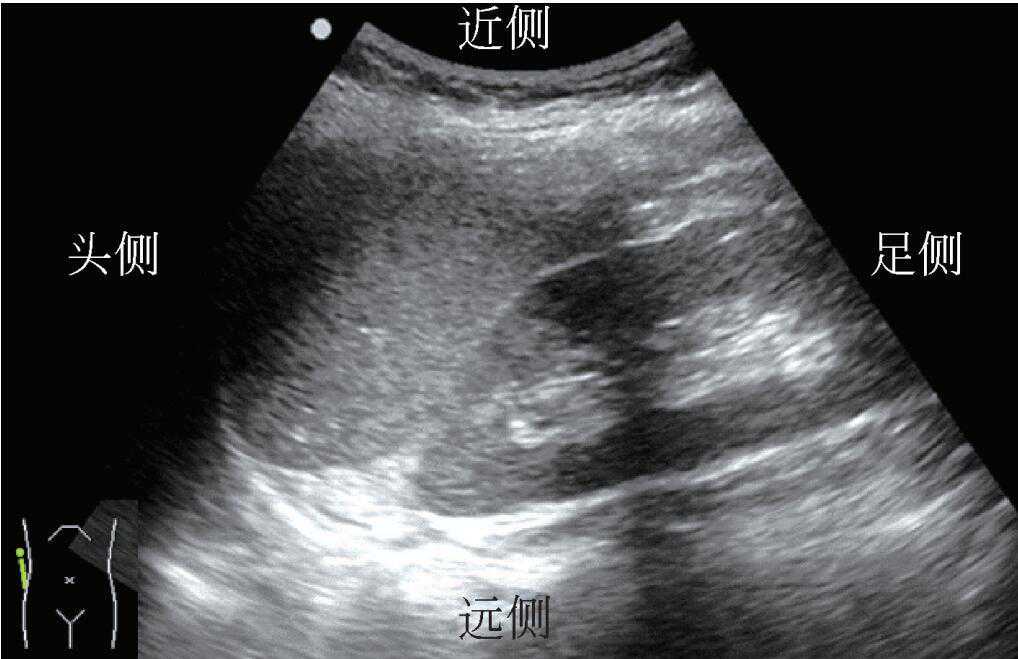

3)探头置于患者一侧横向扫查时为冠状切面。若探头标记指向患者头侧,则在有标记的屏幕侧的结构为患者头侧结构。接近探头的部分位于屏幕上方,远离探头的部分位于屏幕底部(图7)。

图7探头位置与声像对应关系(冠状切面)